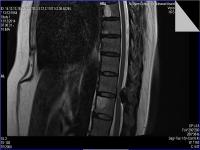

Medical imaging is an important investigative tool will help doctors to reach for the diagnosis of certain diseases, and the the advanced and high-quality imaging technologies are an important factor in maintaining the health of patients and accurate diagnosis of pathological lesions.